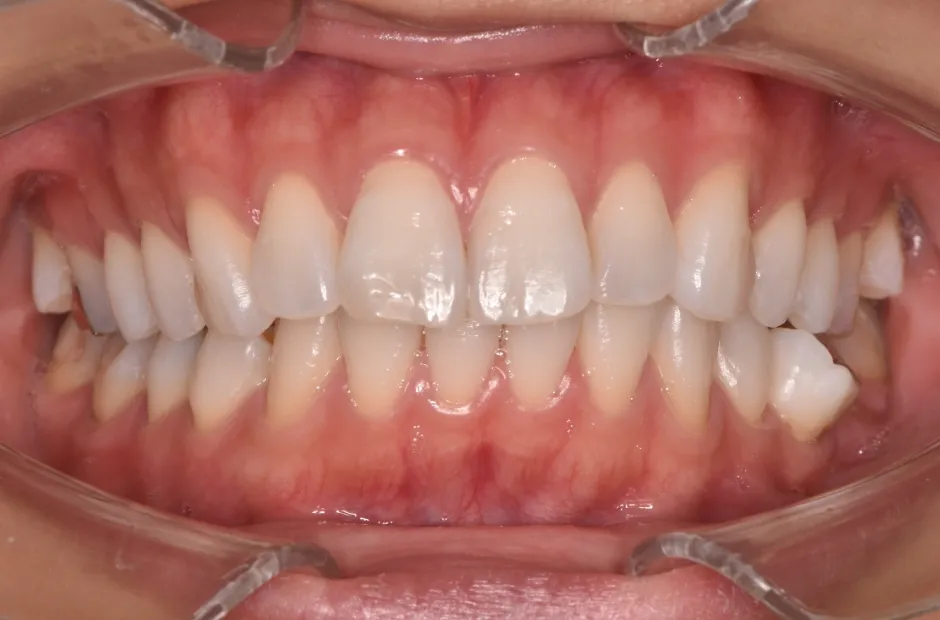

治療後